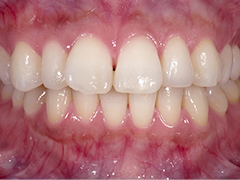

-

ホワイトニング前

ホワイトニング後

治療内容:上顎すべての歯のホワイトニング

治療期間:約2週間

料金:片顎 15,000円(税込)

考えられるリスクや副作用:しみる、効果に個人差がある